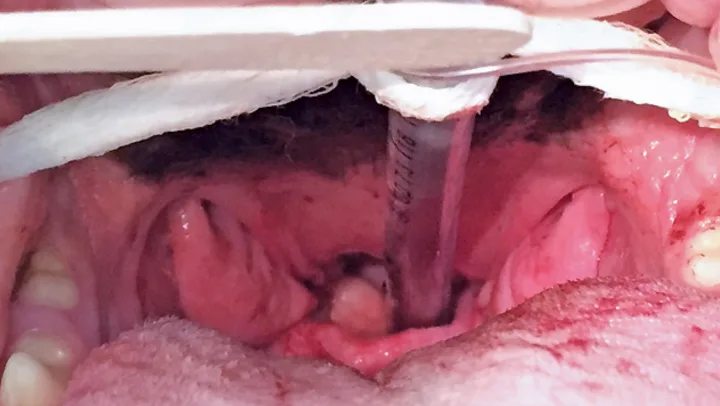

Figure 1 Intraoral view of everted tonsils in the brachycephalic patient. Photos courtesy of Heidi Phillips, VMD, DACVS (Small Animal).

Differential diagnoses included brachycephalic syndrome, laryngeal paralysis, upper airway foreign body, neoplasia, and trauma. Following IV administration of butorphanol and propofol, examination of Maggie’s airway disclosed everted, markedly enlarged palatine tonsils (see Figure 1), an elongated soft palate (see Figure 2), and everted laryngeal saccules (see Figure 3). Visual examination of the larynx during inspiration and expiration showed no laryngeal paralysis, but focal contact of the corniculate and cuneiform processes of the arytenoid cartilages on inspiration confirmed mild Stage III laryngeal collapse. The stages are: